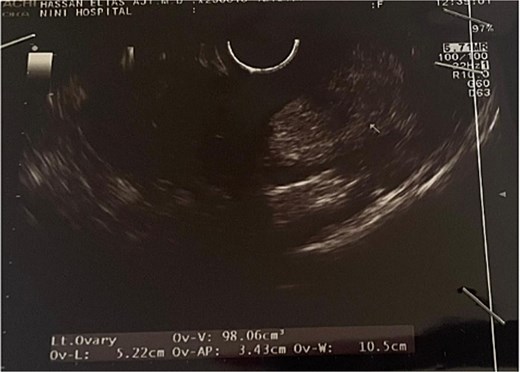

Transvaginal ultrasound revealed a well-circumscribed, heterogeneous uterine mass with mixed echogenicity (Figs 1 and 2). Given the imaging characteristics, a malignant uterine neoplasm, particularly sarcoma, was initially suspected.

Both ovaries were normal in size and morphology, with a few follicles up to 2 cm noted on the left. No pelvic lymphadenopathy or free fluid was identified. The primary finding was a benign uterine fibroid with areas of necrosis and hemorrhage. Due to these concerning radiologic features, the patient underwent a total abdominal hysterectomy and bilateral salpingo-oophorectomy. Histopathological analysis confirmed a myoma with lipomatous differentiation, without evidence of nuclear atypia or mitotic activity. The fallopian tubes were unremarkable, and a functional ovarian cyst was identified. Immunohistochemical staining was negative for malignancy-associated markers including Ki-67 (indicating a low proliferative index), p16, p53, S100, CD34, and HMB-45. Positive staining for desmin and smooth muscle actin confirmed smooth muscle origin. Collectively, these findings support a diagnosis of lipoleiomyoma and effectively rule out sarcoma, confirming the benign nature of the lesion.